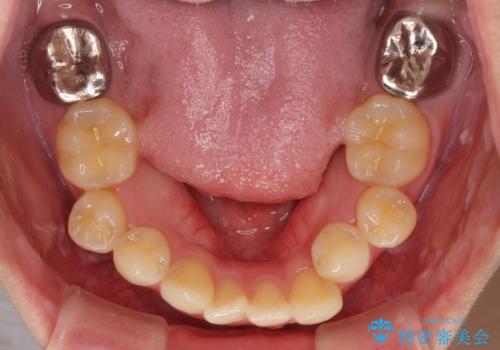

下顎左右大臼歯の歯根部に病変があったため、矯正治療前に根管治療を行い、矯正治療後にセラミッククラウンによる補綴治療を行うこととしました。

下顎前歯と本来抜歯矯正で抜歯する歯とは大きさが異なるため、仕上がりの咬み合わせは理想的なものとはなりませんでしたが、気になっていた八重歯はきれいに改善することができました。